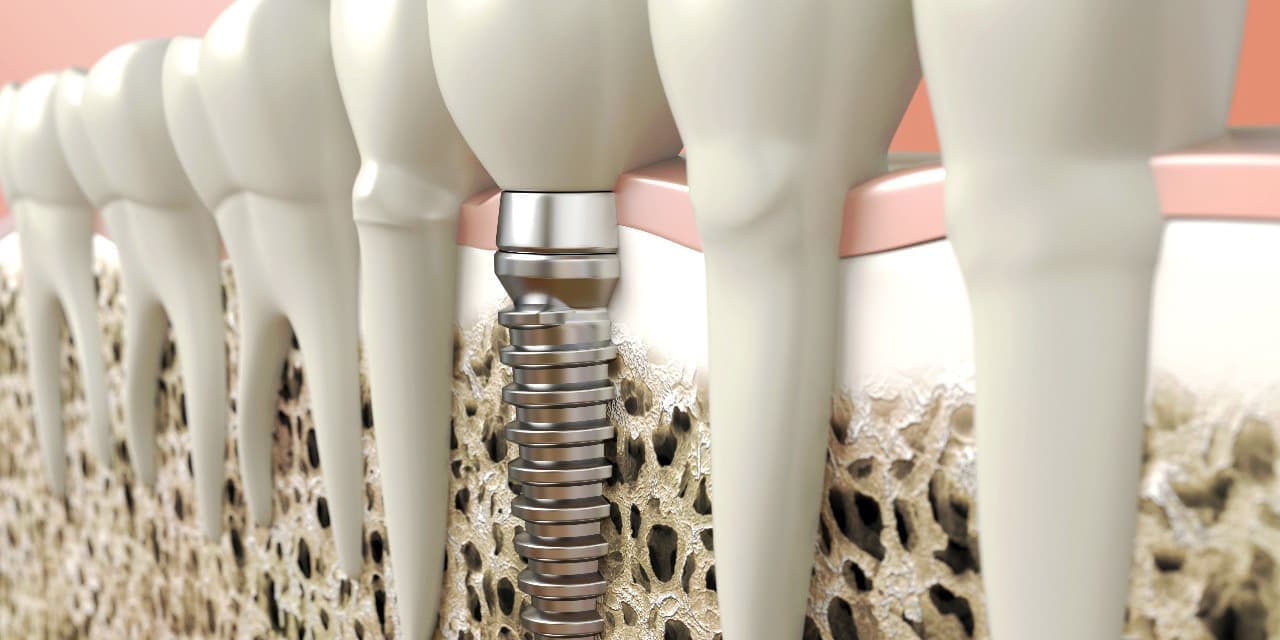

インプラントとは、顎の骨に人工歯根となる金属を埋め込み、その金属を土台にして、天然の歯と同じような人工の歯を取り付ける治療方法です。

埋め込む金属に生体との親和性が高いチタンが使われる事が多く、チタンは長年の臨床研究でインプラントの素材として最も安全であり、また顎の骨としっかり結合することが確認されています。

また顎の骨がやせるのを防げる効果もあります。